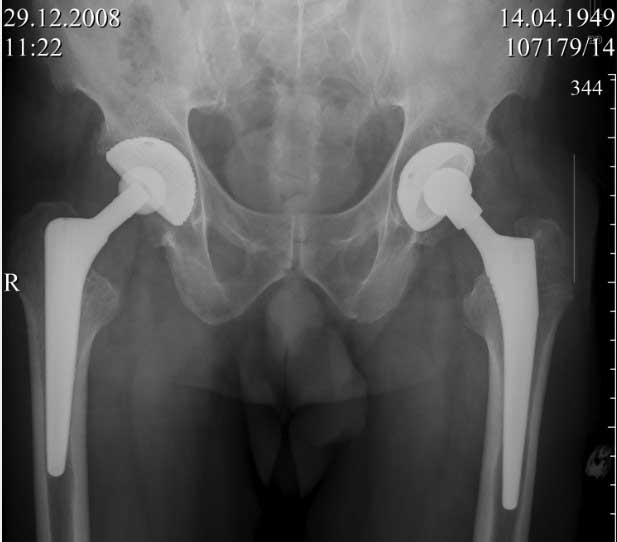

Пациент 60 лет, мужчина. Оперирован в 2007 году, поочередно оперированы два тазобедренных сустава с интервалом в 4 месяца. В 2008 году оперирован на сердце(аорто-коронарное шунтирование).Операция осложнилась инфицированием операционной раны в области грудины, лечился в гнойном отделении.

В конце 2008 года отметил боли в правой паховой области при опоре на правую ногу. На рентген снимках таза с тазобедренными суставами явных признаков нестабильности вертлужного компонента не обнаружено. В 2009 году нейрохирурги его "успешно" прооперировали на L\3-\4 связывая болевой синдром в правой паховой области с наличием грыжи указанного межпозвонкового диска. Состояние только ухудшилось, больной уже не мог долго сидеть, боль прогрессировала . Его в 2009 и 2010 годах смотрел ортопед, делались рентгенснимки, но почему то приходили к выводу что эндопротез справа стабилен. В марте 2011 года я впервые увидел его, через одну неделю после этого был прооперирован. На операции вертлужный компонент при упоре на него инструментом прокручивался во впадине и без труда был извлечен.

ниже снимок в 2008 году

далее снимок в 2009 году

далее снимок у меня на приеме

при этом, у этого пациента была СОЭ 20 мм в час, лейкоциты и формула лейкоцитарная в норме. Можно было пунктировать сустав, но мы этого не сделали и оказались правы: при вскрытии сустава на операции, сустав был сухой и жидкость для посева мы бы не получили.

Но все же, мы провели его лечение как инфицированного, учитывая анамнез: нагноение операционной раны грудины, после операции на сердце. К тому, боли в правом тазобедренном суставе он отметил после осложненной операции на сердце.